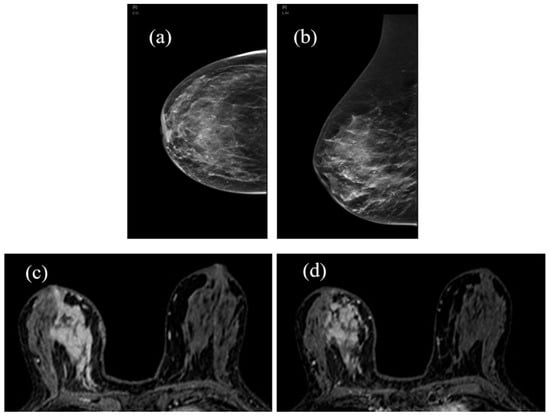

Figure 5, Figure 6 and Figure 7 show three different examples of responses to cancer therapies according to the RECIST criteria.

Figure 6. Partial pathological response (PR): large spiculated neoplastic lesion (4.5 cm) in right retroareolar (HER2 +) with moderate contralateral BPE in the pretreatment baseline image (a). Progressive reduction of lesion diameter is observed to 50% in step I MRI (b) and to 75% in step II MRI (c) without significant changes in BPE.

Figure 7. Stable disease (SD): Mammography shows the presence of a large area of granular microcalcifications in the right lower inner quadrant, unchanged during NAC (a,b). In MRI, it is evident in the same large area of pathological enhancement (c) that does not show significant changes in the extent and activity at the end of therapy. The BPE also appears unchanged (d). Histological type: invasive and in situ non-special type carcinoma (ductal).